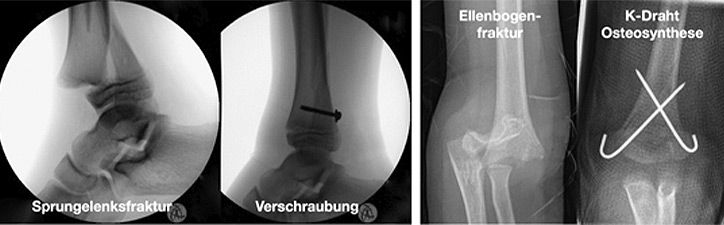

Kirschner-Draht-Osteosynthese

Andere Verfahren der operativen Frakturversorgung im Kindesalter sind die Kirschner-Draht-Osteosynthese, die Verschraubung, der Fixateur und die Plattenosteosynthese. Metallentfernungen werden ambulant durchgeführt, Nachuntersuchungen zum Ausschluss etwaiger Wachstumsstörungen erfolgen in unserer Frakturensprechstunde.